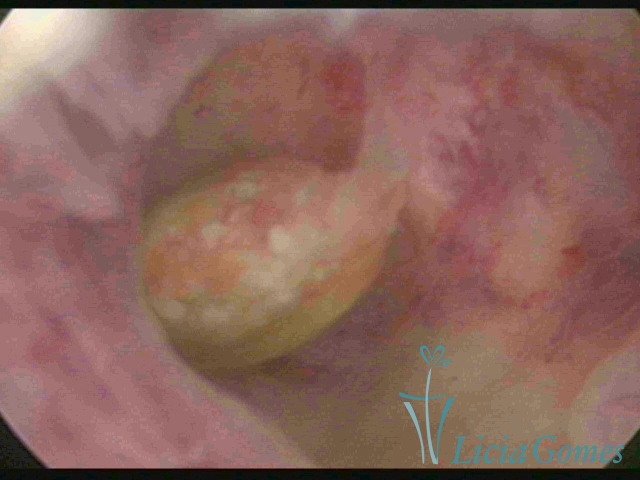

Intact egg cell debris in the uterine cavity

×